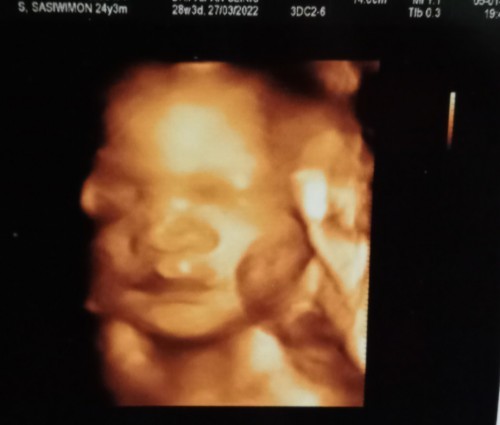

32week ทีมมีนา65 น้องเป็นเด็กผู้ชายค่ะ🥰